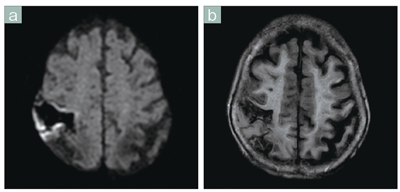

■症例5 頭部の拡散強調画像(陳旧性の脳梗塞の近くに新たな脳梗塞が生じた症例)

a:拡散強調画像 b:FLAIR Brivo

MR355の拡散強調画像(a)は解像度が高く歪みも少ないため,病変の存在だけでなく,位置や範囲の状況も正確に把握できる。この症例は,もともと麻痺があり症状がはっきりしなかったため,拡散強調画像(a)が非常に有用だった。